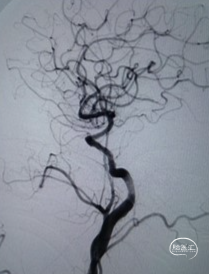

术后影像及检查

影像结论:无残余狭窄,无异常密度影。

术后Tlcl:3级。

影像结论:颅内血管显影良好,无栓塞或造影剂外渗,支架形态良好。术后复查CT无脑出血。